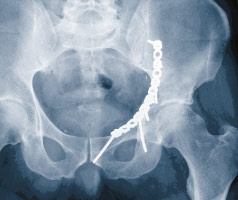

Abb. 3

Das Röntgenbild des Beckens zeigt die Acetabulumfraktur eines 56-jährigen Patienten nach Sturz auf dem Eis mit deutlicher Verschiebung des Oberschenkelkopfes nach innen.

Bei den ersten 20 Patienten mit einem Altersdurchschnitt von 59Jahren – der älteste war 90-jährig – zeigten sich während und nach der Operation keine wesentlichen Komplikationen (Abb. 3). Die Operation dauerte durchschnittlich drei Stunden. In der postoperativen Computertomographie wurde bei 19 Patienten eine anatomische Reposition mit weniger als 1 mm Verschiebung und nur bei einem Patienten eine solche von 2 mm festgestellt. Nach zwei Jahren konnten 17 Patienten nachuntersucht werden. Zwei Patienten erhielten 4 respektive 18 Monate nach der Operation eine Hüfttotalprothese, alle anderen Patienten (88%) hatten eine exzellente oder gute Funktion (Abb. 4). Der «Pararectus»-Zugang ist nicht nur ein minimalinvasiver Zugang, sondern scheint die Versorgung von Acetabulumfrakturen auch bei älteren Patienten zu verbessern. Er sollte jedoch nur von einem erfahrenen Beckenspezialisten angewandt werden, damit bei dieser anspruchsvollen und hochspezialisierten Chirurgie Komplikationen vermieden und gute Ergebnisse erreicht werden.